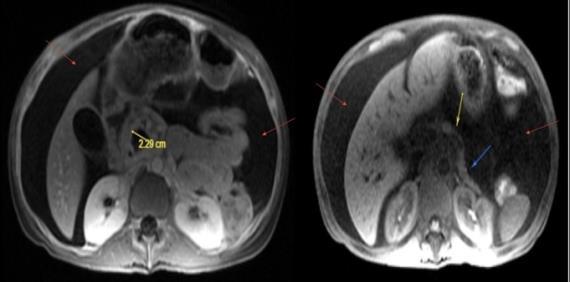

CASE PRESENTATION: A 67-year-old male with a history of partial liver resection, peptic ulcer disease, and Helicobacter pylori gastritis s/p quadruple therapy presented with acute on chronic abdominal pain despite being on a proton pump inhibitor (PPI). He had abdominal pain for the past 5 years associated with nausea, vomiting, diarrhea, and a 50-pound unintentional weight loss. An esophagogastroduodenoscopy (EGD) six months ago demonstrated peptic ulcer disease and Helicobacter pylori which was successfully eradicated.

He underwent a CT-abdomen/pelvis with intravenous contrast in the emergency department which revealed an enhancing 3.4 cm mass in the head of the pancreas with retroperitoneal lymphadenopathy. MRI of the abdomen confirmed the presence of a 3.2 cm enhancing pancreatic head mass with direct extension into the second portion of the duodenum and multiple enlarged retroperitoneal lymph nodes. EGD was remarkable for edema and granularity in the first portion of the duodenum. Endoscopic ultrasound (EUS) was notable for a hypoechoic and heterogeneous irregular mass in the pancreatic head measuring 25 mm by 23 mm in maximal crosssectional diameter with invasion into the serosa and muscularis mucosa of the duodenum. Fine needle aspiration of the pancreatic mass for cytology revealed a well-differentiated pancreatic neuroendocrine tumor (Ki-67 index <1%). Gastrin levels were ordered. He presented again to the hospital 3 weeks later with worsening epigastric abdominal pain and nausea despite adhering to PPI therapy. CT-abdomen revealed new proximal duodenal ulcerations. Gastrin level from the prior admission was noted to be 1988 pg/mL. He subsequently underwent a Whipple's procedure with no complications and was discharged home with a planned EGD surveillance in 6 months.

Figure 1: CT Abdomen and Pelvis with contrast showing a suspicious mass in the second portion of the duodenum/pancreatic head.